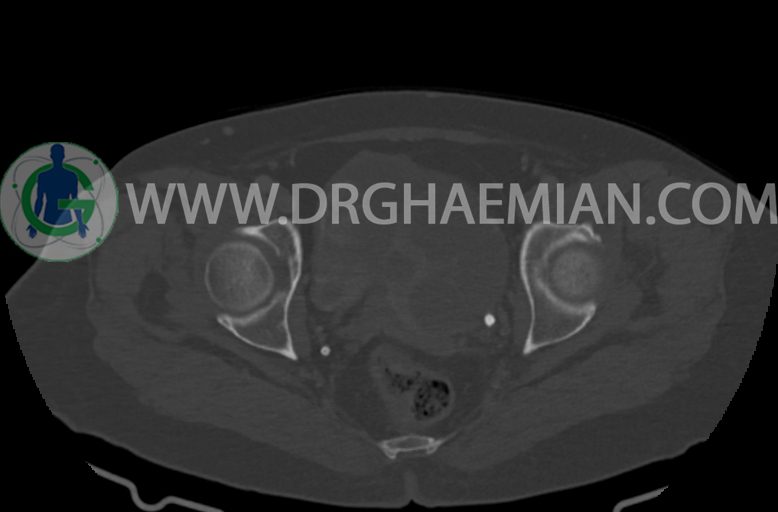

–ضایعه ی mass like هیپردنس- هتروژن به قطر 42mm در سمت راست لگن

–تغییرات DJD در L5/S1

مشهود است.